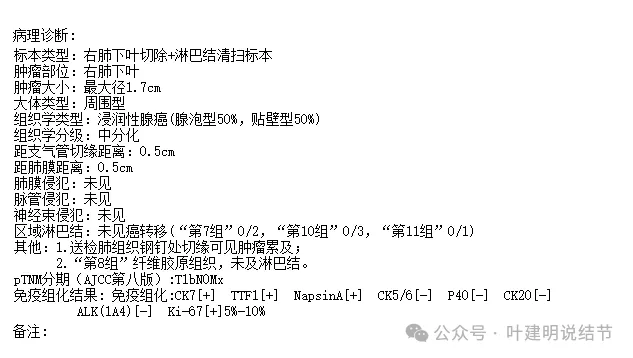

杭州市第一人民医院胸外科叶建明团队为其进行了单孔胸腔镜下微创右下叶切除加淋巴结清扫术。

大体标本切面灰白,质硬,肉眼看就是恶性的。

术中快速病理示浸润性腺癌。

常规病理示:浸润性腺癌,腺泡型50%,贴壁型50%,中分化。淋巴结未见转移。